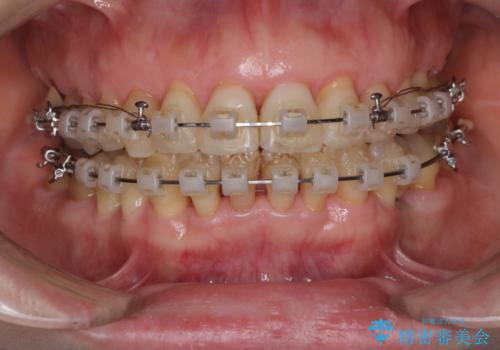

- 矯正装置

- クリアブラケット

- 治療期間

- 2年

近医での歯周病治療の影響でブラックトライアングルが発現していたため、IPR(歯と歯の間を削る)で隙間を改善しつつ、インプラントを固定源に歯列全体を後方へ移動させることとしました。